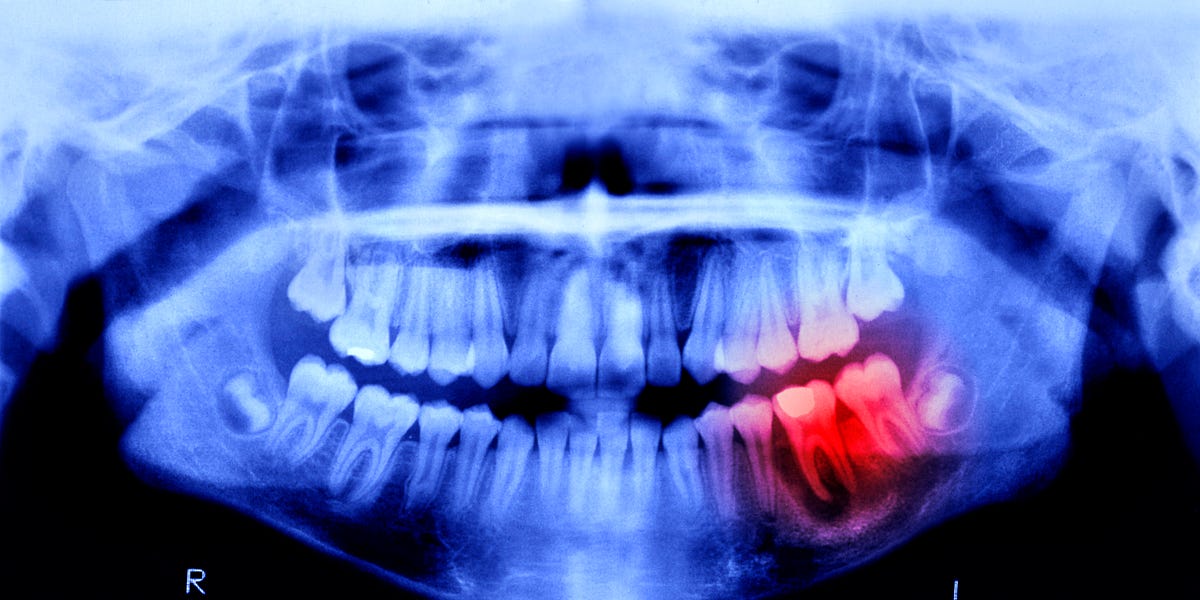

Researchers in Japan have advanced a candidate drug aimed at regenerating human teeth into clinical testing. The experimental approach targets an inhibitor called USAG-1, which earlier animal work in mice and ferrets linked to suppressed tooth development. In 2021, scientists at Kyoto University identified a monoclonal antibody that disrupts the interaction between USAG-1 and bone morphogenetic proteins (BMPs), and subsequent animal results produced renewed interest. Human testing began in September 2024 with an 11-month study enrolling 30 men aged 30 to 64 who are missing at least one tooth; the treatment is given intravenously to evaluate safety and effectiveness. No adverse effects were reported in the prior animal studies, according to the reporting. The team plans later pediatric testing for children aged 2 to 7 missing multiple teeth, and the investigators have said they aim for broader availability of a tooth-regrowing medicine by about 2030 if trials prove successful.